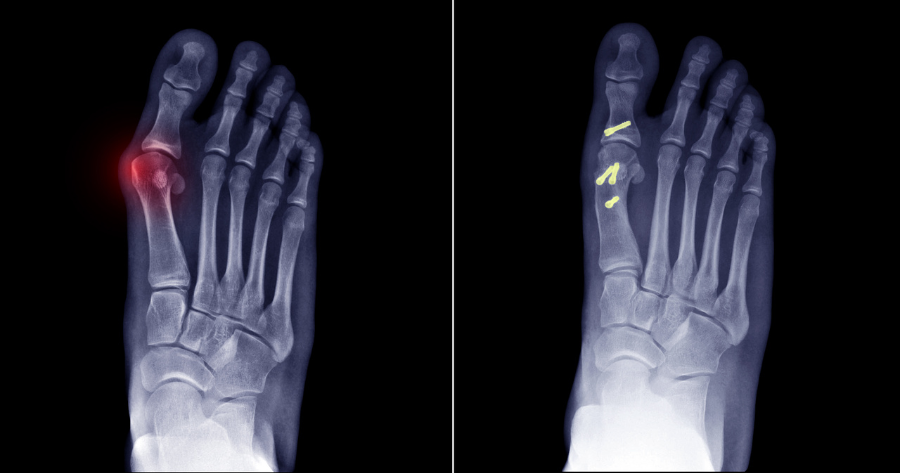

A bunion is a bone and soft tissue deformity between the big toe and the first metatarsal bone, also known as the metatarsophalangeal (MTP) joint. This condition is primarily hereditary but can be aggravated by wearing tight or ill-fitting shoes. Over time, the misalignment causes the big toe to lean toward the second toe, creating a prominent bump. The surrounding tendons and ligaments often become tight, weak, or inflamed, leading to pain, swelling, and difficulty walking.

The procedure involves an incision over the affected area to expose the MTP joint. The surgeon removes the bunion and, in most cases, performs an osteotomy, where a wedge of bone is removed to correct the alignment of the toe. To maintain the new alignment, screws, pins, or plates are often used. Additionally, tendons or ligaments may be lengthened or shortened to ensure optimal joint function. Once the repairs are complete, the incision is closed with sutures, and the foot is carefully bandaged.